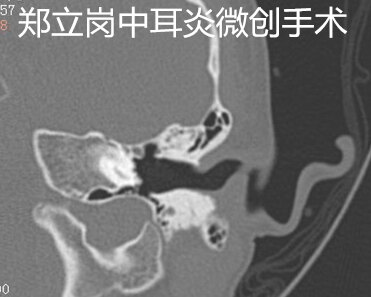

患者黎,男,5岁,广东佛山顺德人,患者于1月余前左耳被棉签戳伤左耳后出现左耳听力下降,伴少许耳出血,一过性耳痛,无眩晕、恶心、呕吐,未予特殊处理。1月前患者左耳进水后,出现短暂耳痛,无耳流脓,未予特殊处理。现为进一步诊治来我院,今门诊以“左侧外伤性鼓膜穿孔”收住入院,拟进一步手术治疗。患者左侧鼓膜大穿孔,这次做的是全麻耳内镜鼓膜穿孔微创手术。插管全麻后就开始了手术,在耳内镜下不用做任何的体表切口,直接翻起外耳道鼓膜皮瓣。翻起皮瓣后可以看到鼓室中无肉芽及胆脂瘤组织,听骨链是完整的,活动可。取合适大小的耳屏软骨修剪后修补鼓膜,鼓膜修补好后检查了两遍确认没问题后就结束了手术。手术用时约40分钟,术后查房患者无明显的不适,无手术相关的并发症。